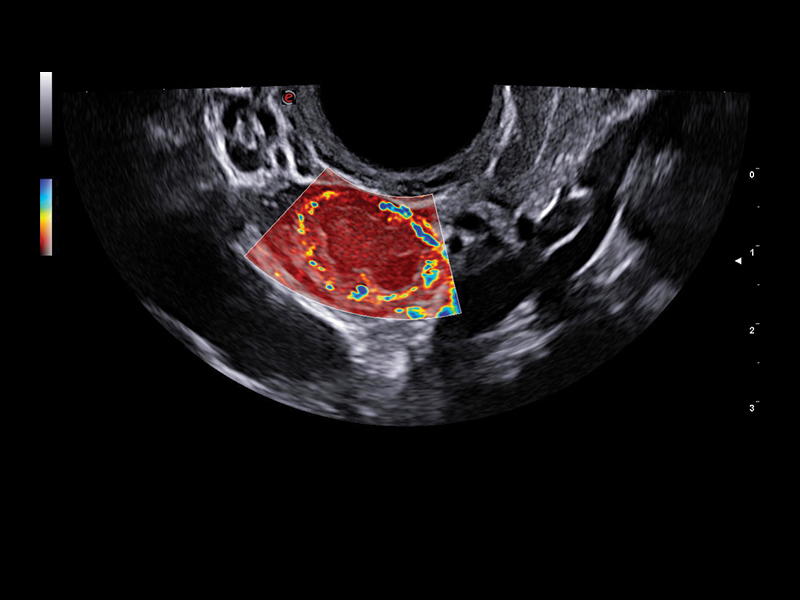

The improved vascular image quality together with the extreme sensitivity of Esaote Doppler technologies (Power Doppler and microV) allow the detection of tiny vessels, to precisely assess the extent of the vascularization, to provide you with a better understanding of certain pelvic abnormalities such as fibroids, polyps, or endometriosis conditions.